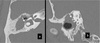

32M w/severe to profound L-sided SNHL and mild R-sided SNHL presents w/cholesteatoma in R ear. He describes having vertigo in environments with loud noises. High resolution CT is pictured What does this patient have?

Labyrinthine fistula (extensive bony destruction forming one cavity resembling operative mastoidectomy).

32M w/severe to profound L-sided SNHL and mild R-sided SNHL presents w/cholesteatoma in R ear. He describes having vertigo in environments with loud noises. High resolution CT is pictured What is the procedure of choice?

Canal wall down mastoidectomy and leave matrix intact over fistula.